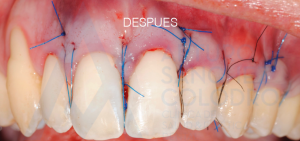

Aquí puede observarse la colocación de la membrana regenerativa

Tras la cirugía mucogingival realizada por el Dr. Arturo Sánchez Colodro en la primera parte de la boca (paciente aún en fase de tratamiento):